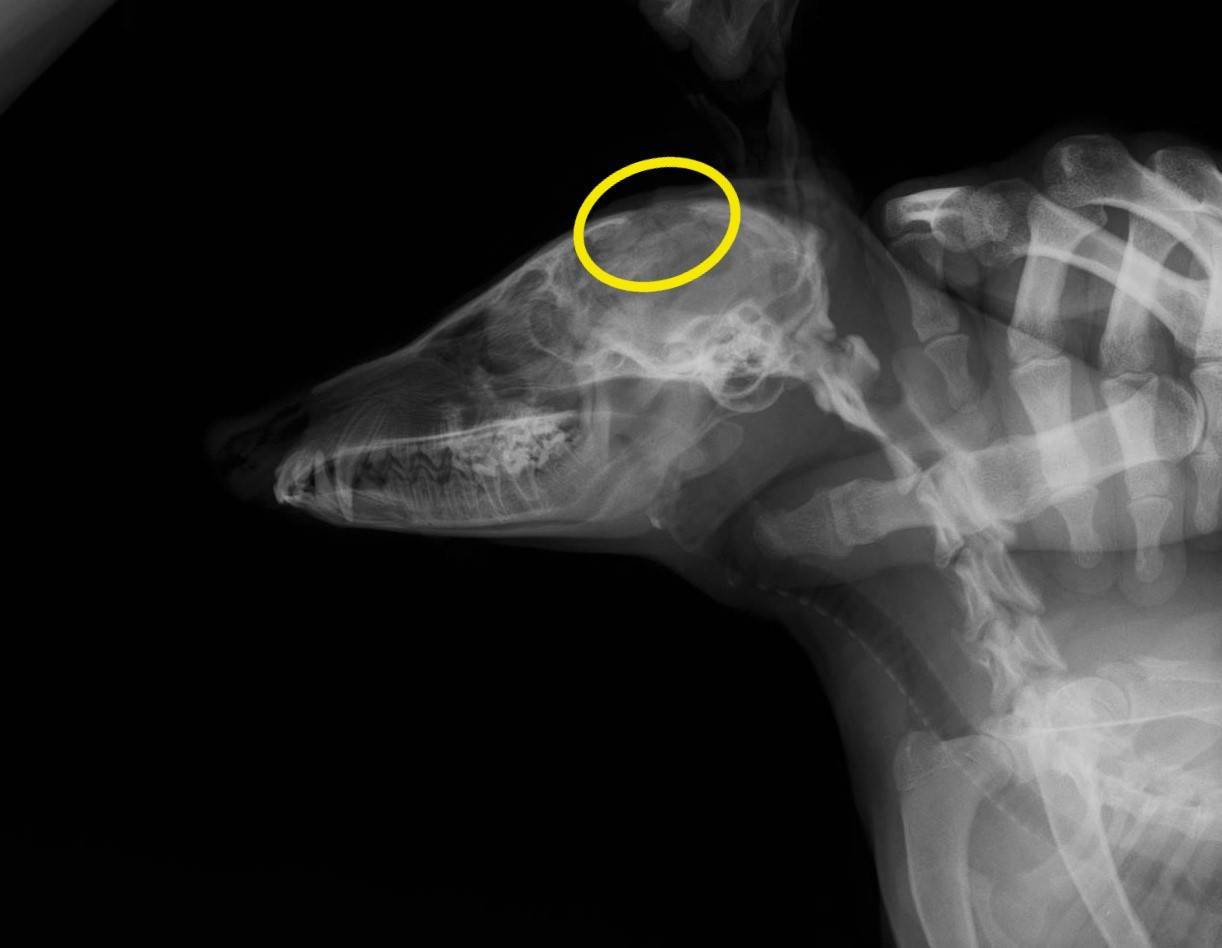

これは、2か月後のX線写真です。

粉々に砕けていた頭蓋骨が増生し、うっすらと覆われています!